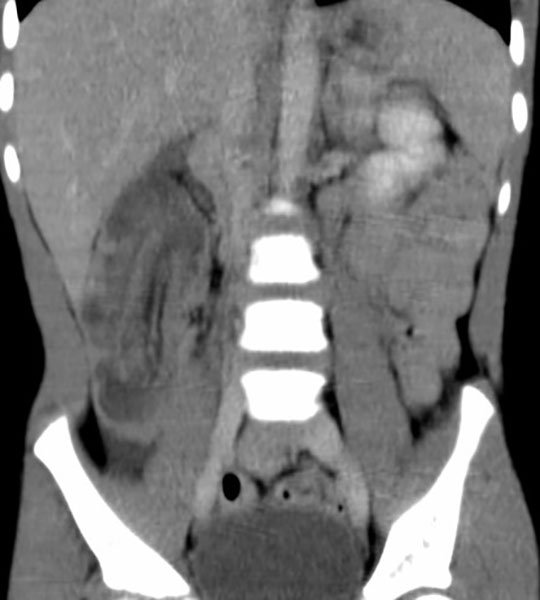

What is intussusception?

Telescoping of a proximal bowel segment into a distal segment, causing obstruction.

Why is intussusception dangerous?

It compresses the mesentery, cutting off blood supply and causing necrosis.

How is intussusception classified?

Idiopathic and degenerative.

In which age group does intussusception most commonly occur?

Infants and young children (>90% of cases).

What causes intussusception?

Peristalsis forcing bowel into itself.

Why does obstruction occur in intussusception?

Bowel contents cannot pass through the telescoped segment.

Where does intussusception most commonly occur in children?

At the ileocecal valve.

Why does intussusception occur in children?

Often due to loose mesentery allowing excessive bowel movement.

What usually causes intussusception in adults?

An underlying pathology such as a polyp, inflammatory mass, or carcinoma.

Can intussusception occur anywhere in adults?

Yes, in both the small and large bowel.

What is transient intussusception?

A temporary form that resolves spontaneously, often seen on CT in celiac disease.

What are classic symptoms of intussusception in children?

Sudden severe abdominal pain, distension, vomiting, and a palpable right-sided mass.

What is 'red currant jelly' stool?

Stool mixed with blood and mucus, classic for pediatric intussusception.

What symptoms occur in adults with intussusception?

Recurrent abdominal pain, nausea, and vomiting.

Why is prompt treatment critical in intussusception?

Mortality is <1% if treated within 24 hours but rises sharply after 48 hours.

How is intussusception treated in children?

Air or water-soluble contrast enema.

How is intussusception treated in adults?

Enema plus investigation and correction of the underlying cause.

When is surgery required for intussusception?

If enema treatment is unsuccessful.